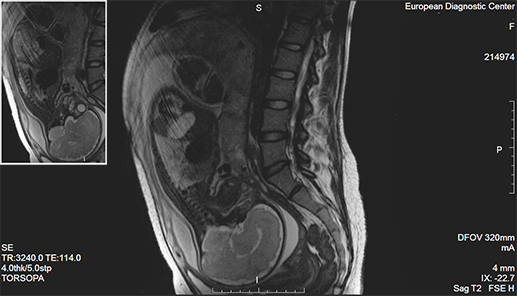

Ирина об МРТ

https://www.baby.ru/blogs/post/385574521-237168372/

На 17 неделе делали МРТ брюшной полости. Сначала боялась, но боли стали такими, что на все стало наплевать. Уже не думала, МРТ при беременности можно или нет. Процедуру проходила в Европейском диагностическом центре в течение 15 минут и поставили диагноз: острый панкреатит. Осложнений для ребенка никаких. Сейчас ему полмесяца и все хорошо

Так как МРТ плода при беременности до 4 месяцев не делают, на процедуру приходят женщины, у которых уже виден живот. Но никаких проблем не будет. Томограф напоминает тоннель с выдвижной кушеткой. Пациент размещается на кушетке, и в зависимости от обследования помещается внутрь аппарата, или нет. Предварительно перед погружением в томограф нужно надеть одежду без пуговиц и снять все металлические предметы.

Важно сохранять неподвижность на протяжении всей процедуры, то есть 20-30 минут.

После того, как обследование закончится, идет сигнал и аппарат отключается.

Почему-то часто страх у женщин возникает, когда их направляют наМРТ головного мозга при беременности. Но это не страшно, так как обследование вообще не касается плода. Пациент просто ложится на кушетку, а вокруг обследуемой области – головы – устанавливаются датчики. Вот почему можно ли делать беременным МРТ головы, не опасаясь за плод.